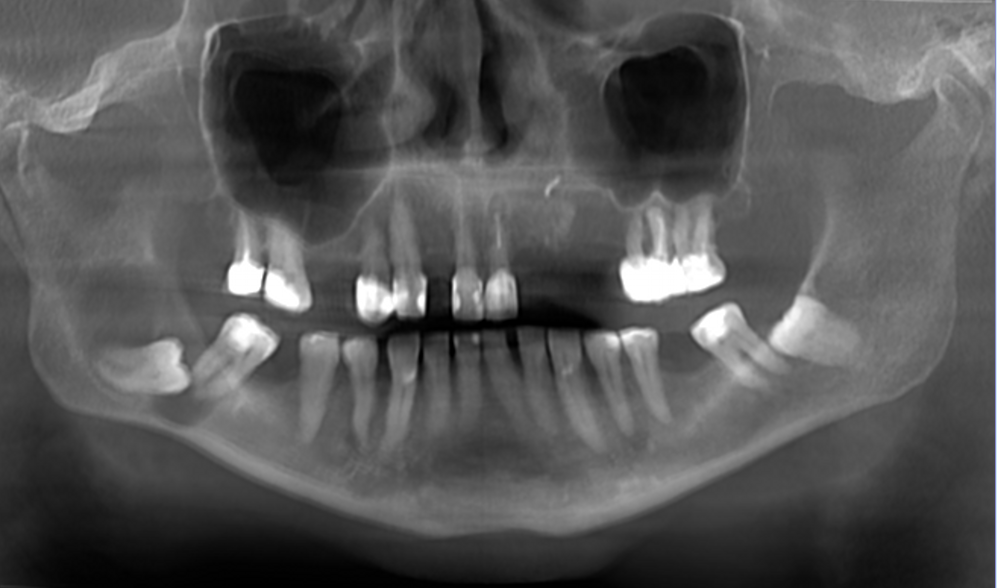

Pacjentka przyjmowała na stałe rywaroksaban i kwas acetylosalicylowy z powodu zakrzepicy żył głębokich kończyn dolnych oraz leki na nadciśnienie tętnicze – walsartan i amlodypinę. W badaniu zewnątrzustnym nie stwierdzono odchyleń od normy. W badaniu wewnątrzustnym stwierdzono chełbotanie wyczuwalne od strony przedsionkowej i językowej po stronie prawej żuchwy. W badaniu CBCT stwierdzono zmianę o charakterze osteolitycznym wielkości 43 mm × 41 mm × 12 mm (w największym wymiarze), która zajmowała prawy trzon, kąt i gałąź żuchwy oraz obejmowała drugi (ząb 47) oraz trzeci ząb trzonowy (ząb 48). Zmiana perforowała blaszkę zbitą od strony przedsionkowej i językowej (ryc. 1). Zaplanowano zabieg w znieczuleniu miejscowym. Dobę przed zabiegiem u pacjentki wdrożono antybiotykoterapię w postaci klindamycyny (300 mg), stosowanej co 8 godzin.

Ryc. 1. Badanie CBCT: a) rekonstrukcja pantomograficzna; b) przekrój poprzeczny; c) przekrój strzałkowy – widoczna zmiana o charakterze osteolizy, związana z zatrzymanym zębem 48 (listopad 2020).